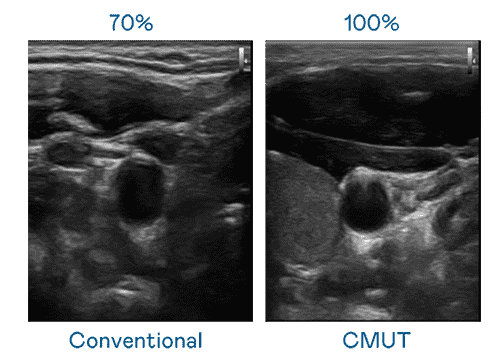

CMUT 技术是一种用电容式微机电元件来产生超音波讯号的技术。。与传统 PZT 压电式技术相比,,CMUT 频宽增加 30%,,,更宽频的超音波讯号让影像解析度大幅提升,,,,是实现高影像品质医疗超音波扫描、、、、促进精准医疗发展的关键技术。。。

超音波影像的解析度高低,,,,首先取决于探头能发出的讯号频宽。。。。尊龙集团 CMUT 可提供高清晰的超音波讯号,,,提供高频宽、、、、高灵敏度、、、、影像纹理细节更高的超音波影像,,,协助医护人员缩短影像判读时间及利用精准的医疗影像进行诊断。。。。